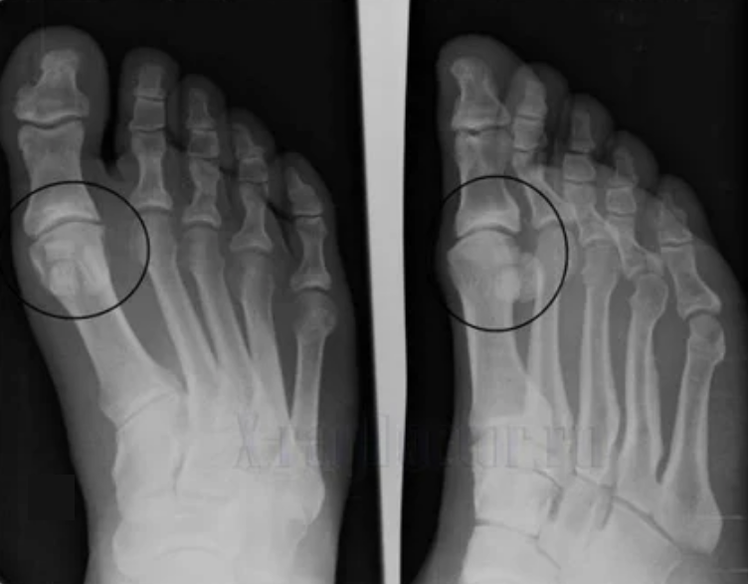

To make a diagnosis, rheumatologists study the patient's complaints and prescribe an X-raffle examination.Most often, radiography is used in 2 projections.The doctor examines the presence of dystrophic disorders in hyalin cartilage and bone joints.If the joint space is reduced, the bones are deformed or flattened, there are cystic formations on the surface of the cartilage, osteophytes are signs of osteoarthritis.During the inspection, osteoarthritis indicates the instability of the joint: the axis of the members and the subluxation is disturbed.

Often, an X-Ray image is unable to provide complete information on the state of the joint.For a more in -depth study, computed tomography is prescribed, it is effective in examining the bones.MRI is more often used to study soft tissue.